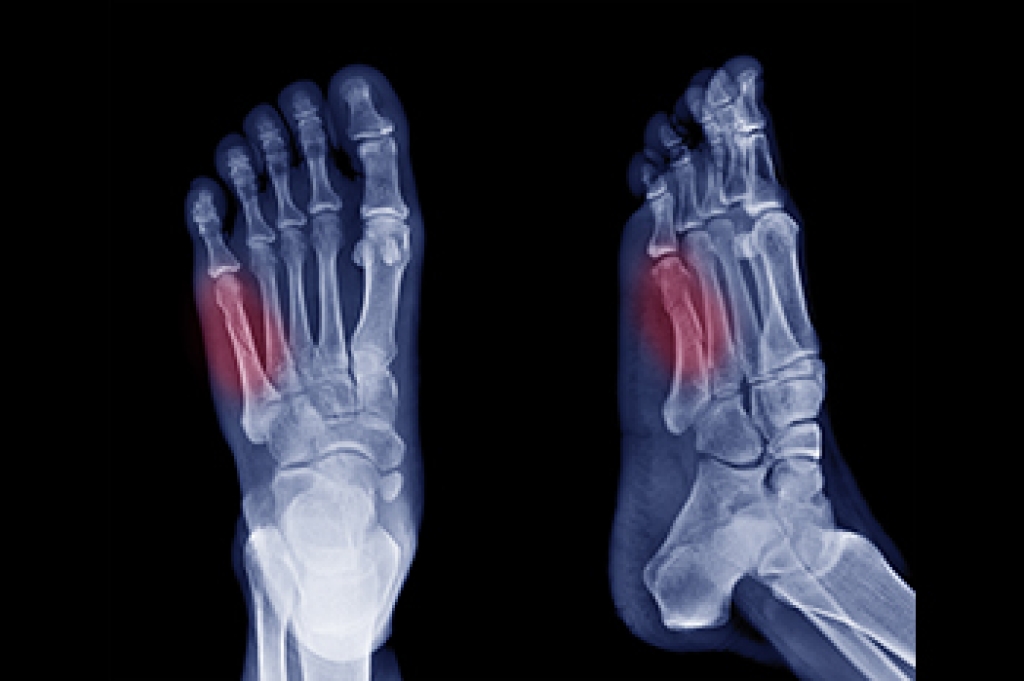

How Does an Ankle Sprain Occur?

Ankle sprains take place when the ligaments in your ankle are torn or stretched beyond their limits. There are multiple ways that the ankle can become injured, including twisting or rolling over onto your ankle, putting undue stress on it, or causing trauma to the ankle itself.

What Are the Symptoms?

- Mild to moderate bruising

- Limited mobility

- Swelling

- Discoloration of the skin (depending on severity)

Treatment of a Sprain

Treatment of a sprain depends on the severity. Many times, people are told to rest and remain off their feet completely, while others are given an air cast. If the sprain is very severe, surgery may be required.